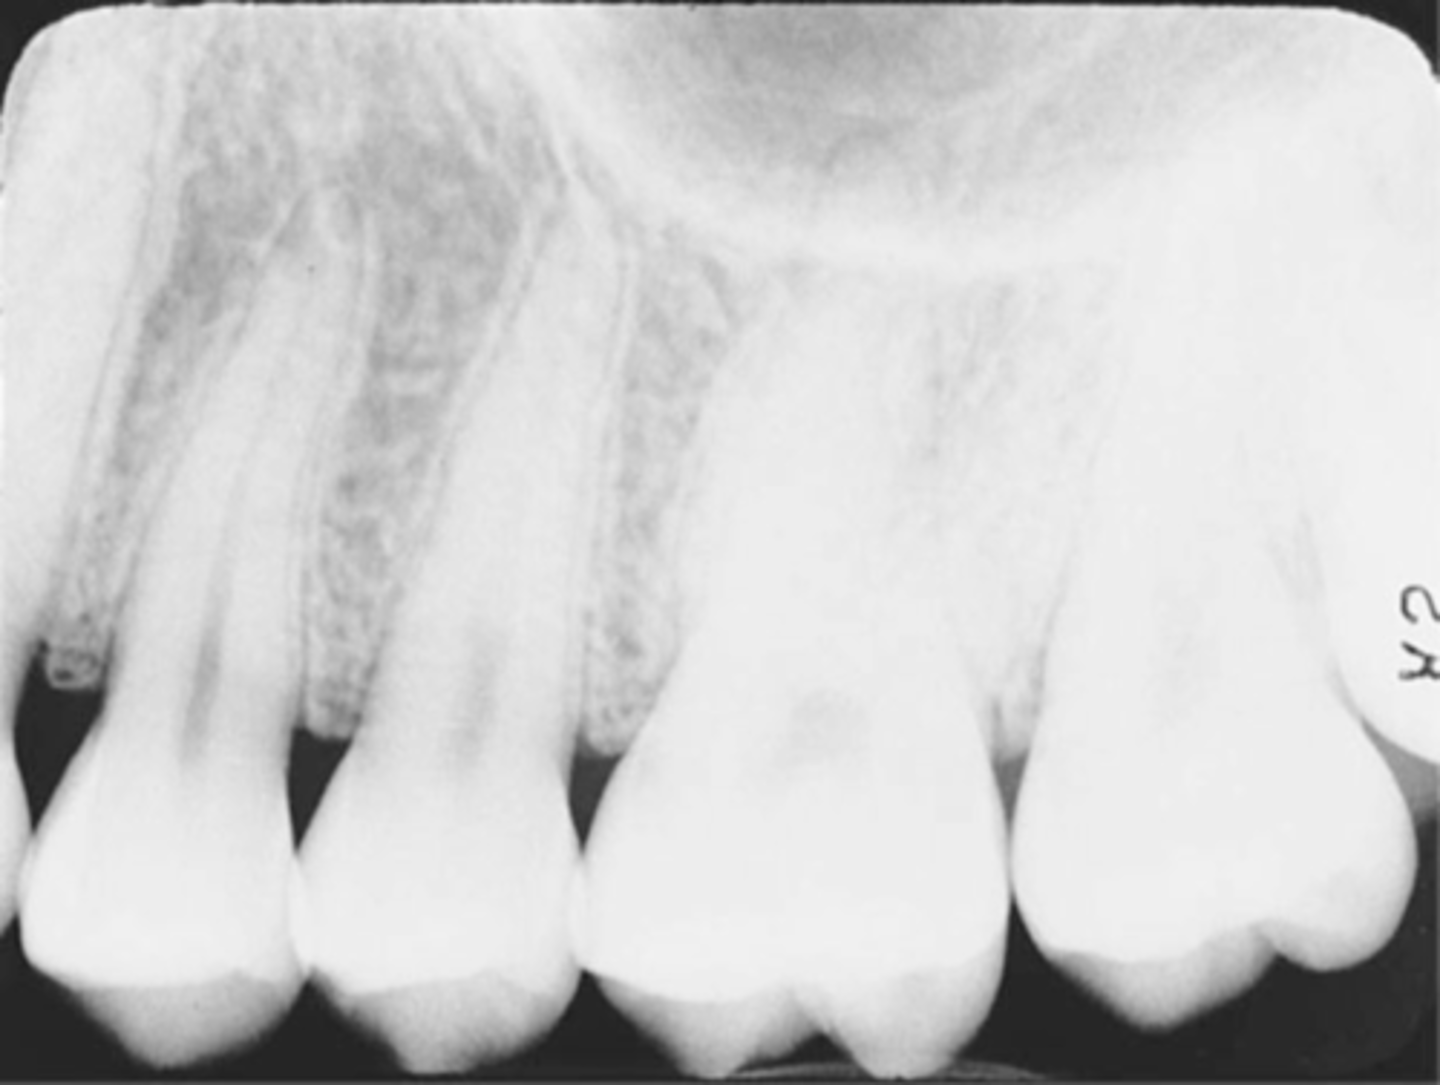

Incorrect Horizontal Angulation -->Bite-Wing

-Overlapped contacts

-CR was not directed through the interproximal spaces.

Mesiodistal overlap

-The x-ray beam is directed obliquely from mesial to distal

Cause - If overlapping is more severe in the posterior region, cone is angled too much form the mesial.

Correction - Shift the PID toward the posterior or direct the CR more from the distal

Distomesial overlap

-The x-ray beam is directed obliquely from distal to mesial

Cause - If overlapping is more in the anterior region, cone is angled too much from the distal

Correction - Shift the PID toward the anterior, direct the central ray beam more from the mesail